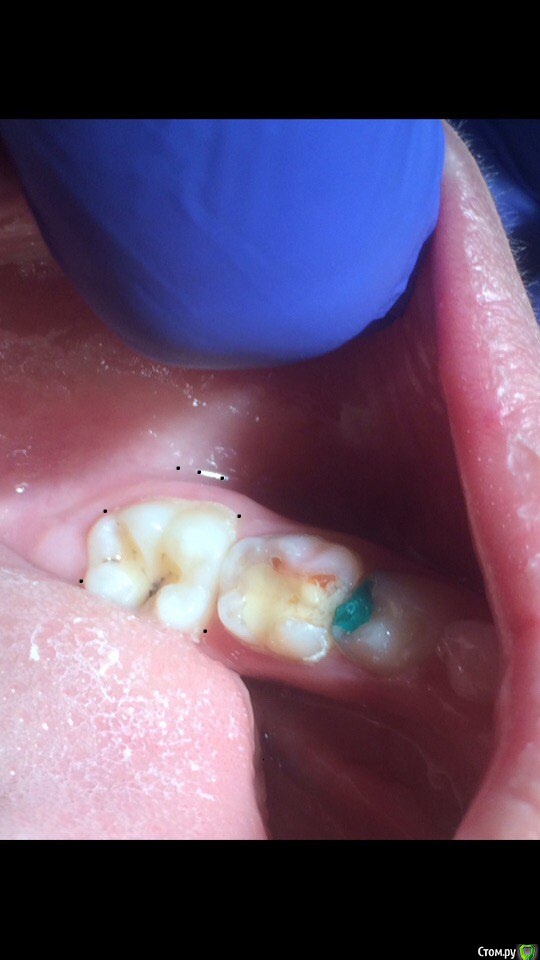

Wrestrus66 Опубликовано 12 октября, 2016 Поделиться Опубликовано 12 октября, 2016 ещё раз всем привет..стаж работы пол года..и вот одна из проблем это 6 в возрасте от 6-12 лет ..не получается делать проводниковую ищу другие выходы..По фото правильно ли я выбираю место вкола инфильрата и сосочки??я уже не знаю что и делать.. Именно туда уколол я и всё равно где эт черная пигментация пациент испытывал сильную прям боль Ссылка на комментарий

Wrestrus66 Опубликовано 12 октября, 2016 Автор Поделиться Опубликовано 12 октября, 2016 вот фото т.е с вколом Ссылка на комментарий

crown Опубликовано 12 октября, 2016 Поделиться Опубликовано 12 октября, 2016 вот фото т.е с вколом Док не извращайтесь. Там толстенная кость, инфильтрация по сосочкам не поможет. Интралигаментарная еще может помочь, но техника сложна и очень болезненно. Тренируйтесь делать проводниковую. Я делаю мандибулярную и добавляю инфильтрацию, если эффекта нет повторно мандибулярную, процент успеха высокий Ссылка на комментарий

Kota Опубликовано 12 октября, 2016 Поделиться Опубликовано 12 октября, 2016 Ого. Сколько мест укола. Не проще ли одну мандибулярку(хотя в ней тоже минусы есть) Я делаю не так, но у меня аппарат STA, по этому мой совет вам не поможет. Ссылка на комментарий